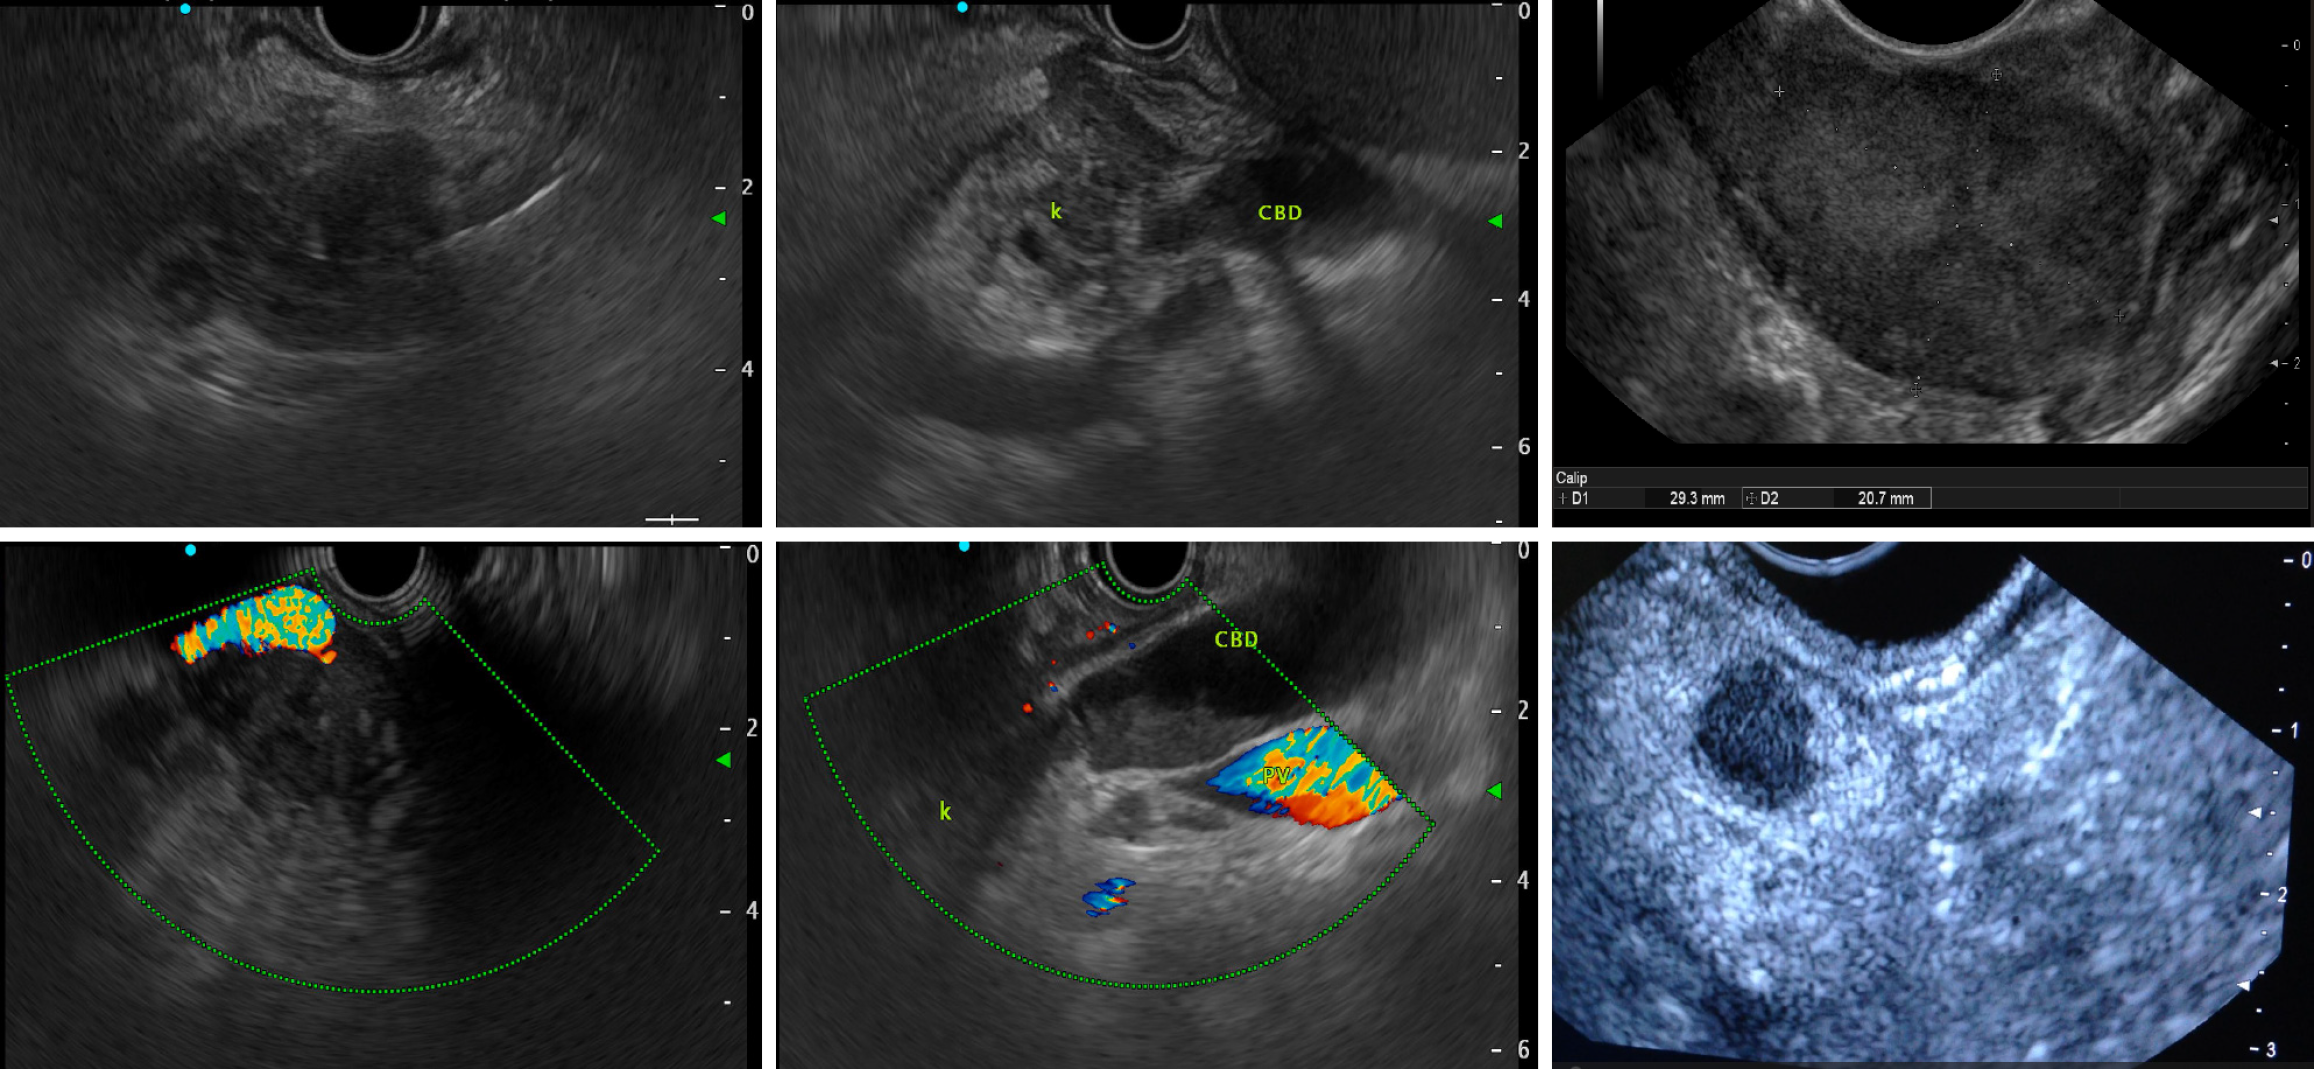

Figure 2

Figure 2 In the first row, there is a hypoechoic neoplasm with irregular margins, a common bile duct invasion, and the measurement of the lesion in B-mode. In the second row, you can see an arterial invasion, a portal vein invasion, and a homogeneous neuroendocrine tumor with regular margins.